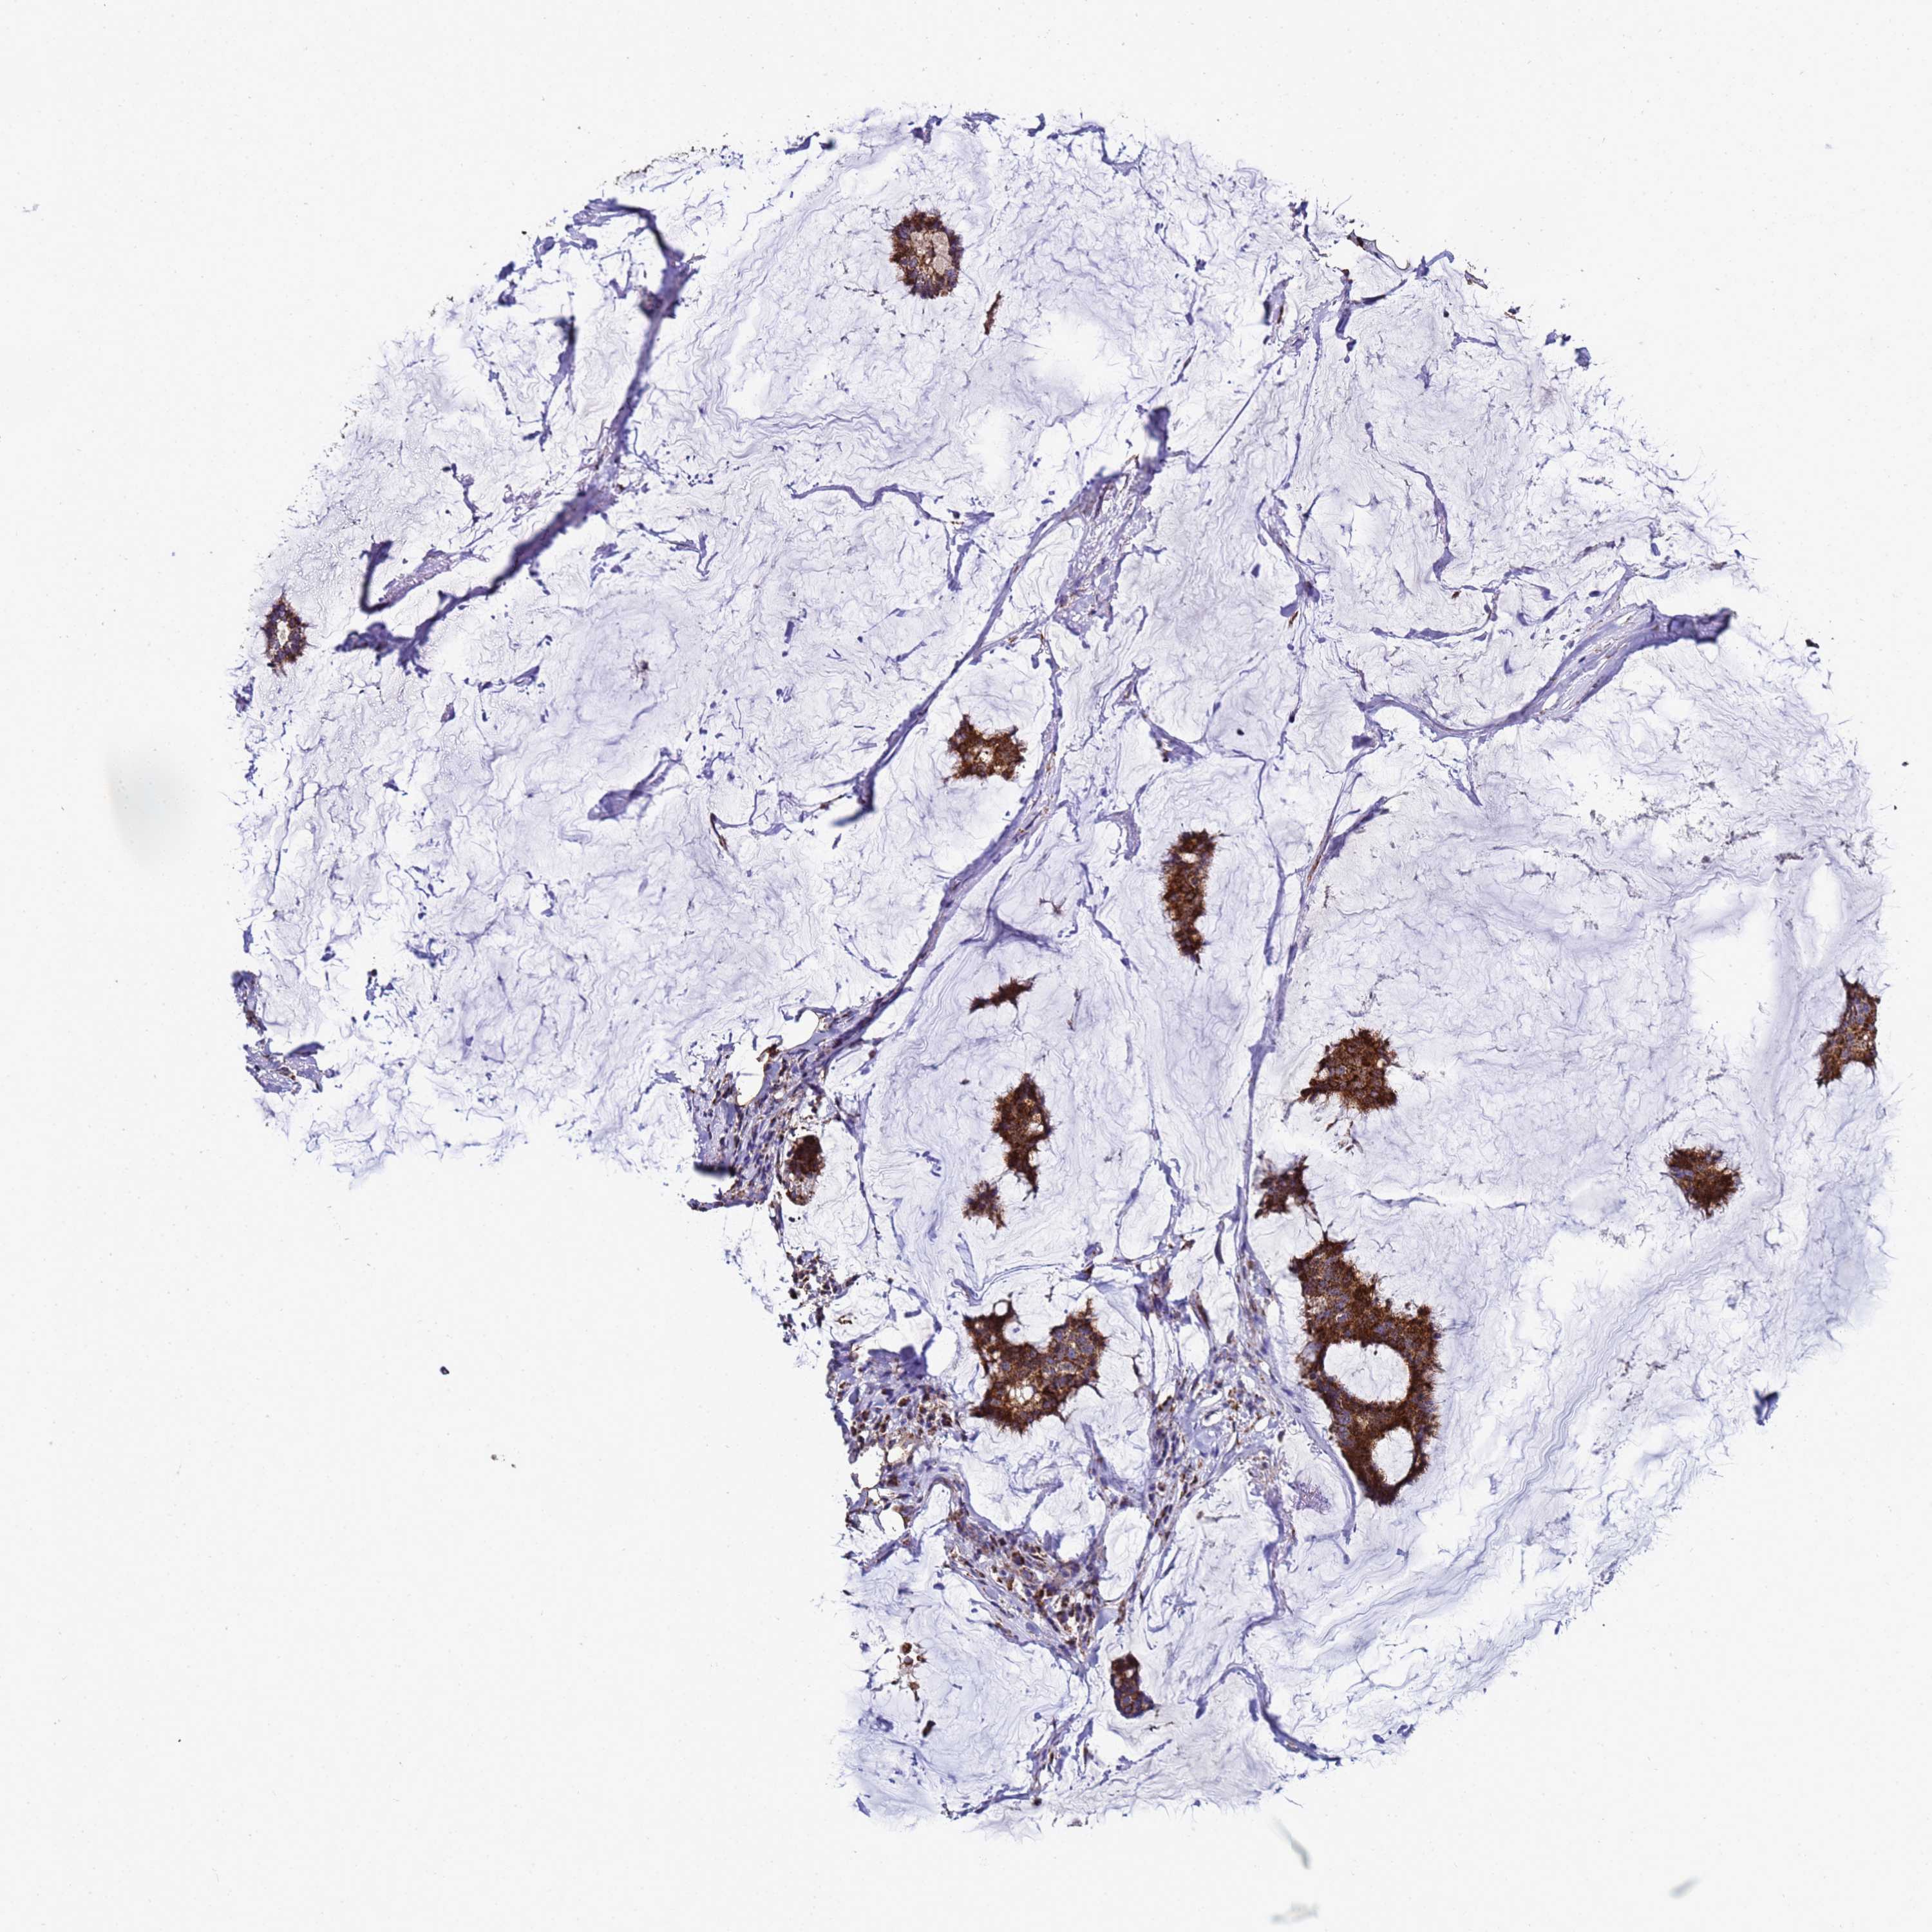

CANCER BREAST CANCER Show tissue menu

BRCA TCGA BRCA VALIDATION PROTEIN EXPRESSION

ANTIBODIES

AND

VALIDATION